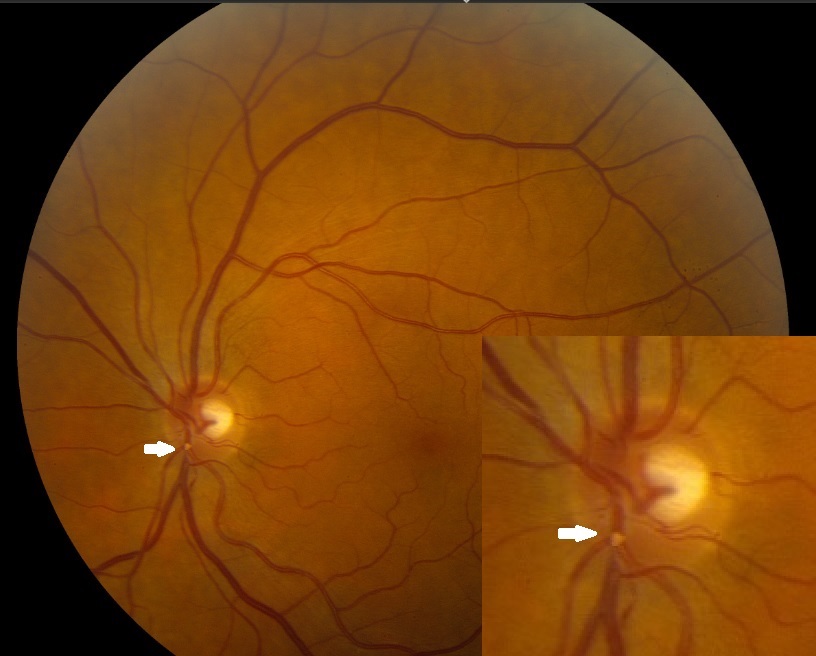

Атрофия зрительного нерва Лебера: Симптомы и лечение